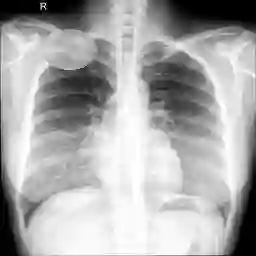

Large numbers of labeled medical images are essential for the accurate detection of anomalies, but manual annotation is labor-intensive and time-consuming. Self-supervised learning (SSL) is a training method to learn data-specific features without manual annotation. Several SSL-based models have been employed in medical image anomaly detection. These SSL methods effectively learn representations in several field-specific images, such as natural and industrial product images. However, owing to the requirement of medical expertise, typical SSL-based models are inefficient in medical image anomaly detection. We present an SSL-based model that enables anatomical structure-based unsupervised anomaly detection (UAD). The model employs the anatomy-aware pasting (AnatPaste) augmentation tool. AnatPaste employs a threshold-based lung segmentation pretext task to create anomalies in normal chest radiographs, which are used for model pretraining. These anomalies are similar to real anomalies and help the model recognize them. We evaluate our model on three opensource chest radiograph datasets. Our model exhibit area under curves (AUC) of 92.1%, 78.7%, and 81.9%, which are the highest among existing UAD models. This is the first SSL model to employ anatomical information as a pretext task. AnatPaste can be applied in various deep learning models and downstream tasks. It can be employed for other modalities by fixing appropriate segmentation. Our code is publicly available at: https://github.com/jun-sato/AnatPaste.